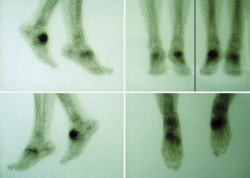

Se realizó estudio mediante tomografía computarizada (TC) (Figura 3) donde podemos ver la falta de fusión de la osteotomía de la primera cuña, los cambios degenerativos escafocuneanos, la fusión de la tercera cuña con el cuboides y el hundimiento de la columna medial a nivel transcuneano.

Figura 3. Imágenes de la tomografía computarizada.